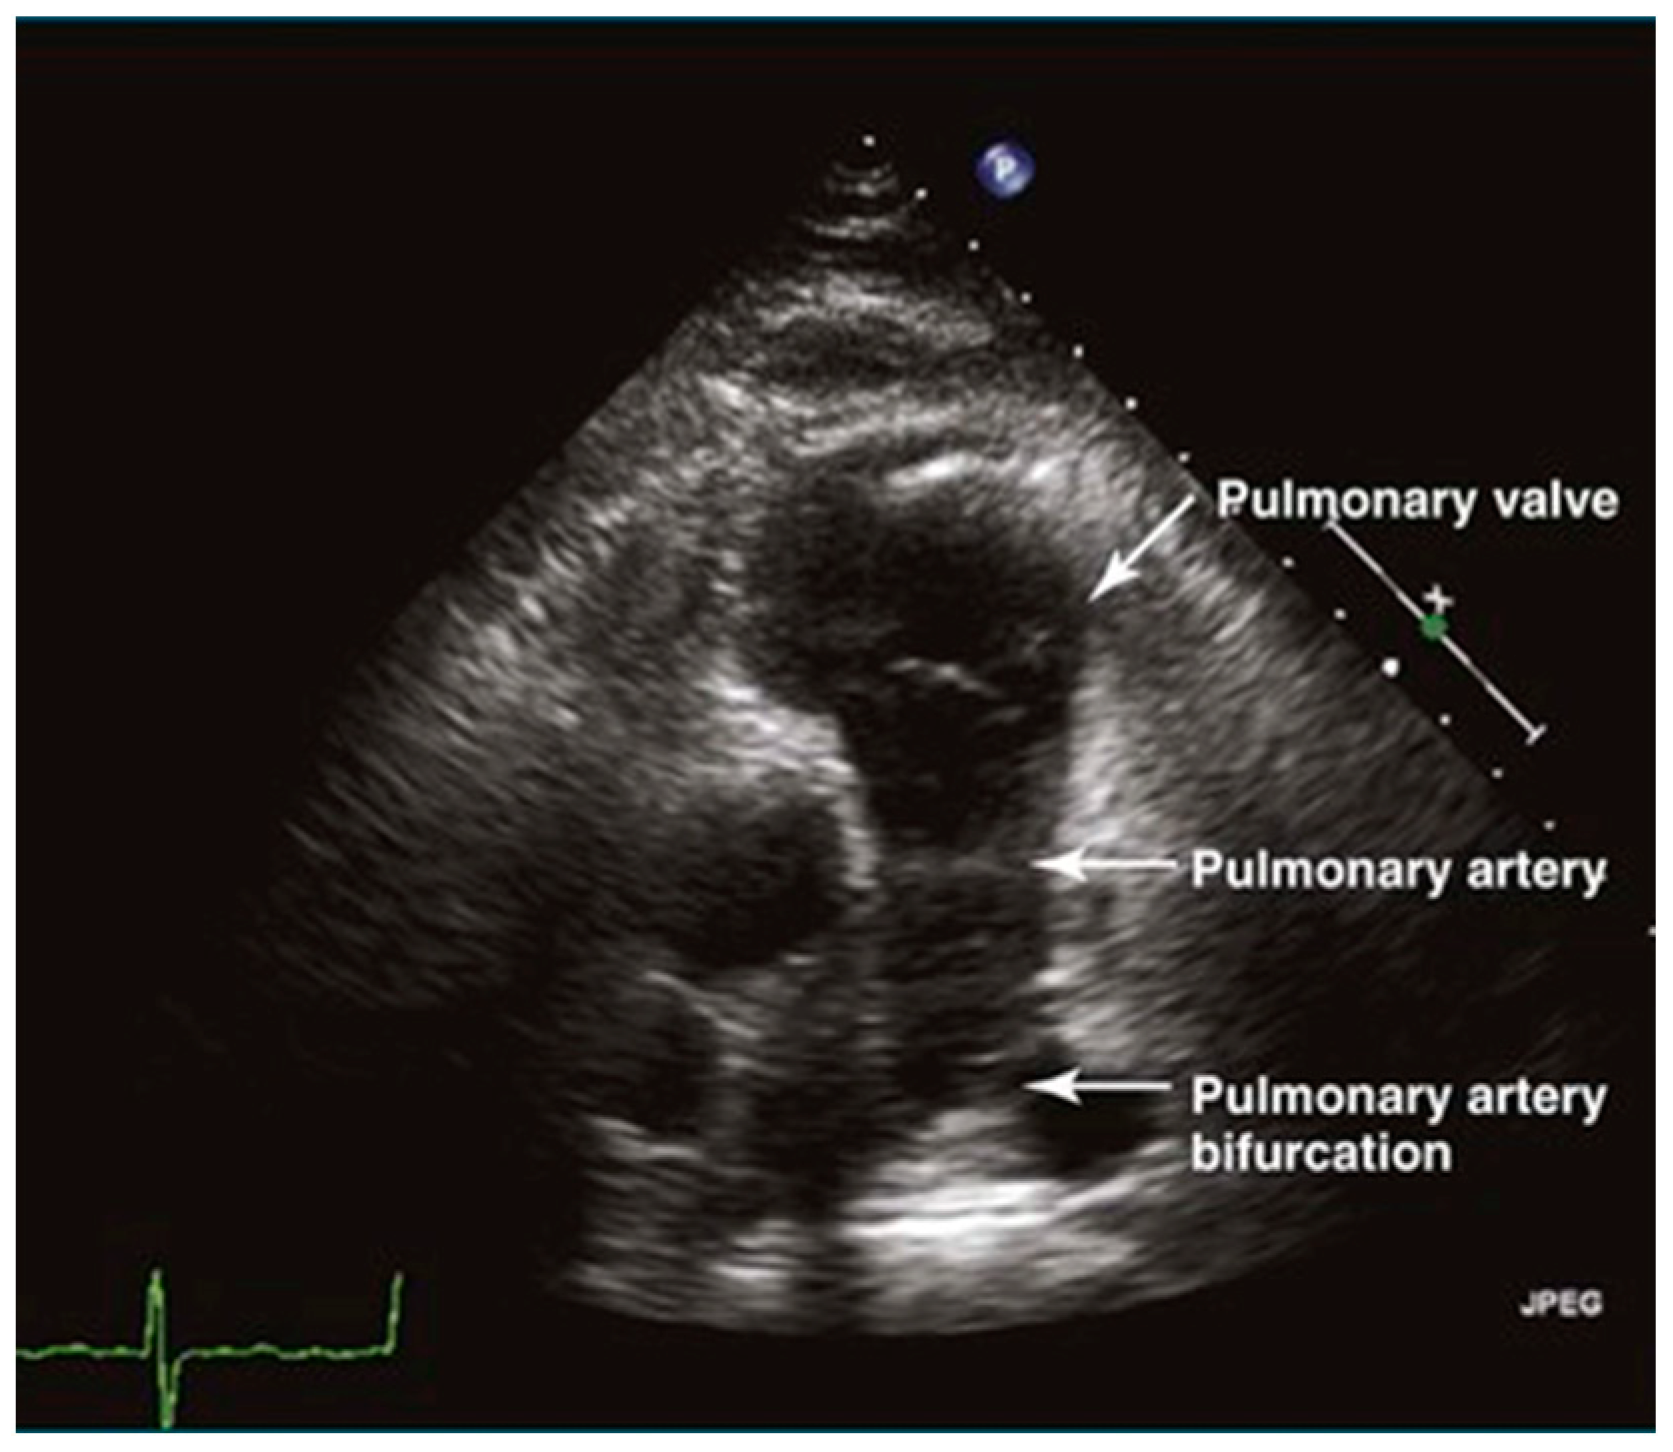

3.1.3. Pulmonary Artery

The long-axis view of the pulmonary artery shows the main pulmonary artery and its branches, aiding in the identification of space-occupying lesions like thrombi (Figure 5). This view is crucial for diagnosing acute pulmonary embolism. Additionally, the width of the main pulmonary artery helps differentiate between acute and chronic pulmonary hypertension, with significant widening indicating the chronic form [14].

Figure 5.

The sign of pulmonary artery in long-axis view.